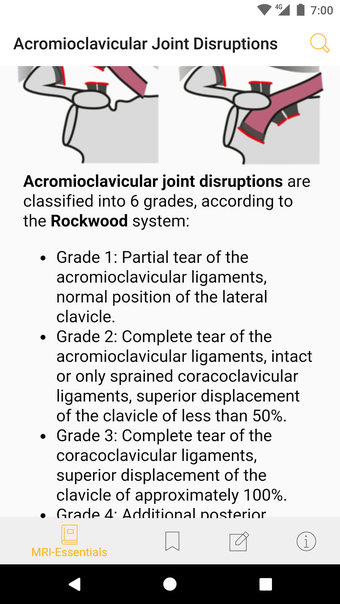

Die Basisversion liefert die wesentlichen Fakten, die immer noch kurz und prägnant sind. Die Fakten konzentrieren sich auf die klinisch relevanten Aspekte des Zustands des Patienten.

Die Pro-Version enthält mehr als 4.000 hochwertige Bilder von herausragender Bildqualität, die den Text veranschaulichen. Sie sind so konzipiert, dass sie dem Leser einen schnellen Überblick über die wichtigsten Informationen zum Zustand geben.